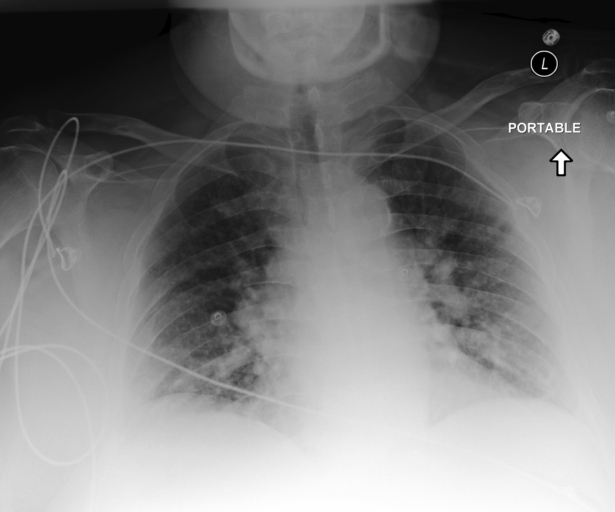

Examples of Qwen2.5-0.5B-PRM predictions on MAIRA-2 generated findings. Background: Verifier Correct, Verifier Incorrect. Border: GT Correct, GT Incorrect. Underlined: Verifier prediction differs from GT. shown.

Probabilities: 0.480, 0.786, 0.103, 0.082

Report:

The lungs are clear.

Negative for pleural effusion or pneumothorax.

Cardiomediastinal silhouette is within normal limits.

There are atherosclerotic aortic calcifications.